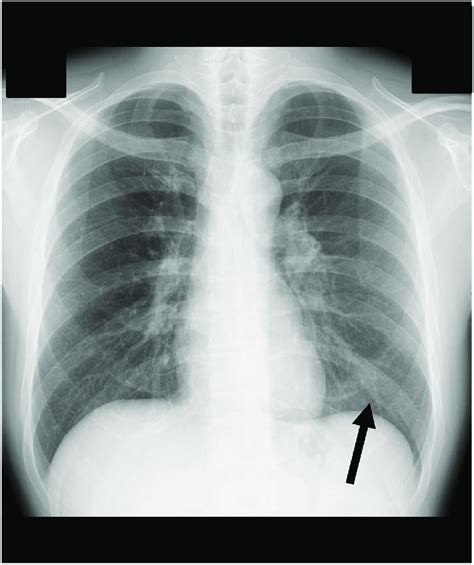

One of the hallmark X-ray findings in pneumonia is focal consolidation. This refers to a localized area of lung tissue filled with fluid or pus, appearing as a dense, white patch on the X-ray. This consolidation represents the infected area of the lung, distinguishing pneumonia from bronchitis.

In contrast, bronchitis typically does not present with focal consolidation. The inflammation in bronchitis is primarily confined to the airways, and the lung tissue itself remains relatively clear on X-ray.

Observing or not observing focal consolidation is a crucial differentiator between pneumonia and bronchitis on X-ray.

Diffuse Lung Markings in Bronchitis

Bronchitis often presents with diffuse lung markings on X-ray, appearing as increased linear shadows throughout the lungs. These markings represent thickened bronchial walls and increased mucus within the airways. This is a characteristic feature of chronic bronchitis.

While pneumonia might also exhibit increased lung markings, they are often localized to the infected area. The diffuse nature of the increased markings in bronchitis helps distinguish it from the more localized pattern seen in pneumonia.

Analyzing the distribution of lung markings on X-ray is essential for differentiating between these two conditions.